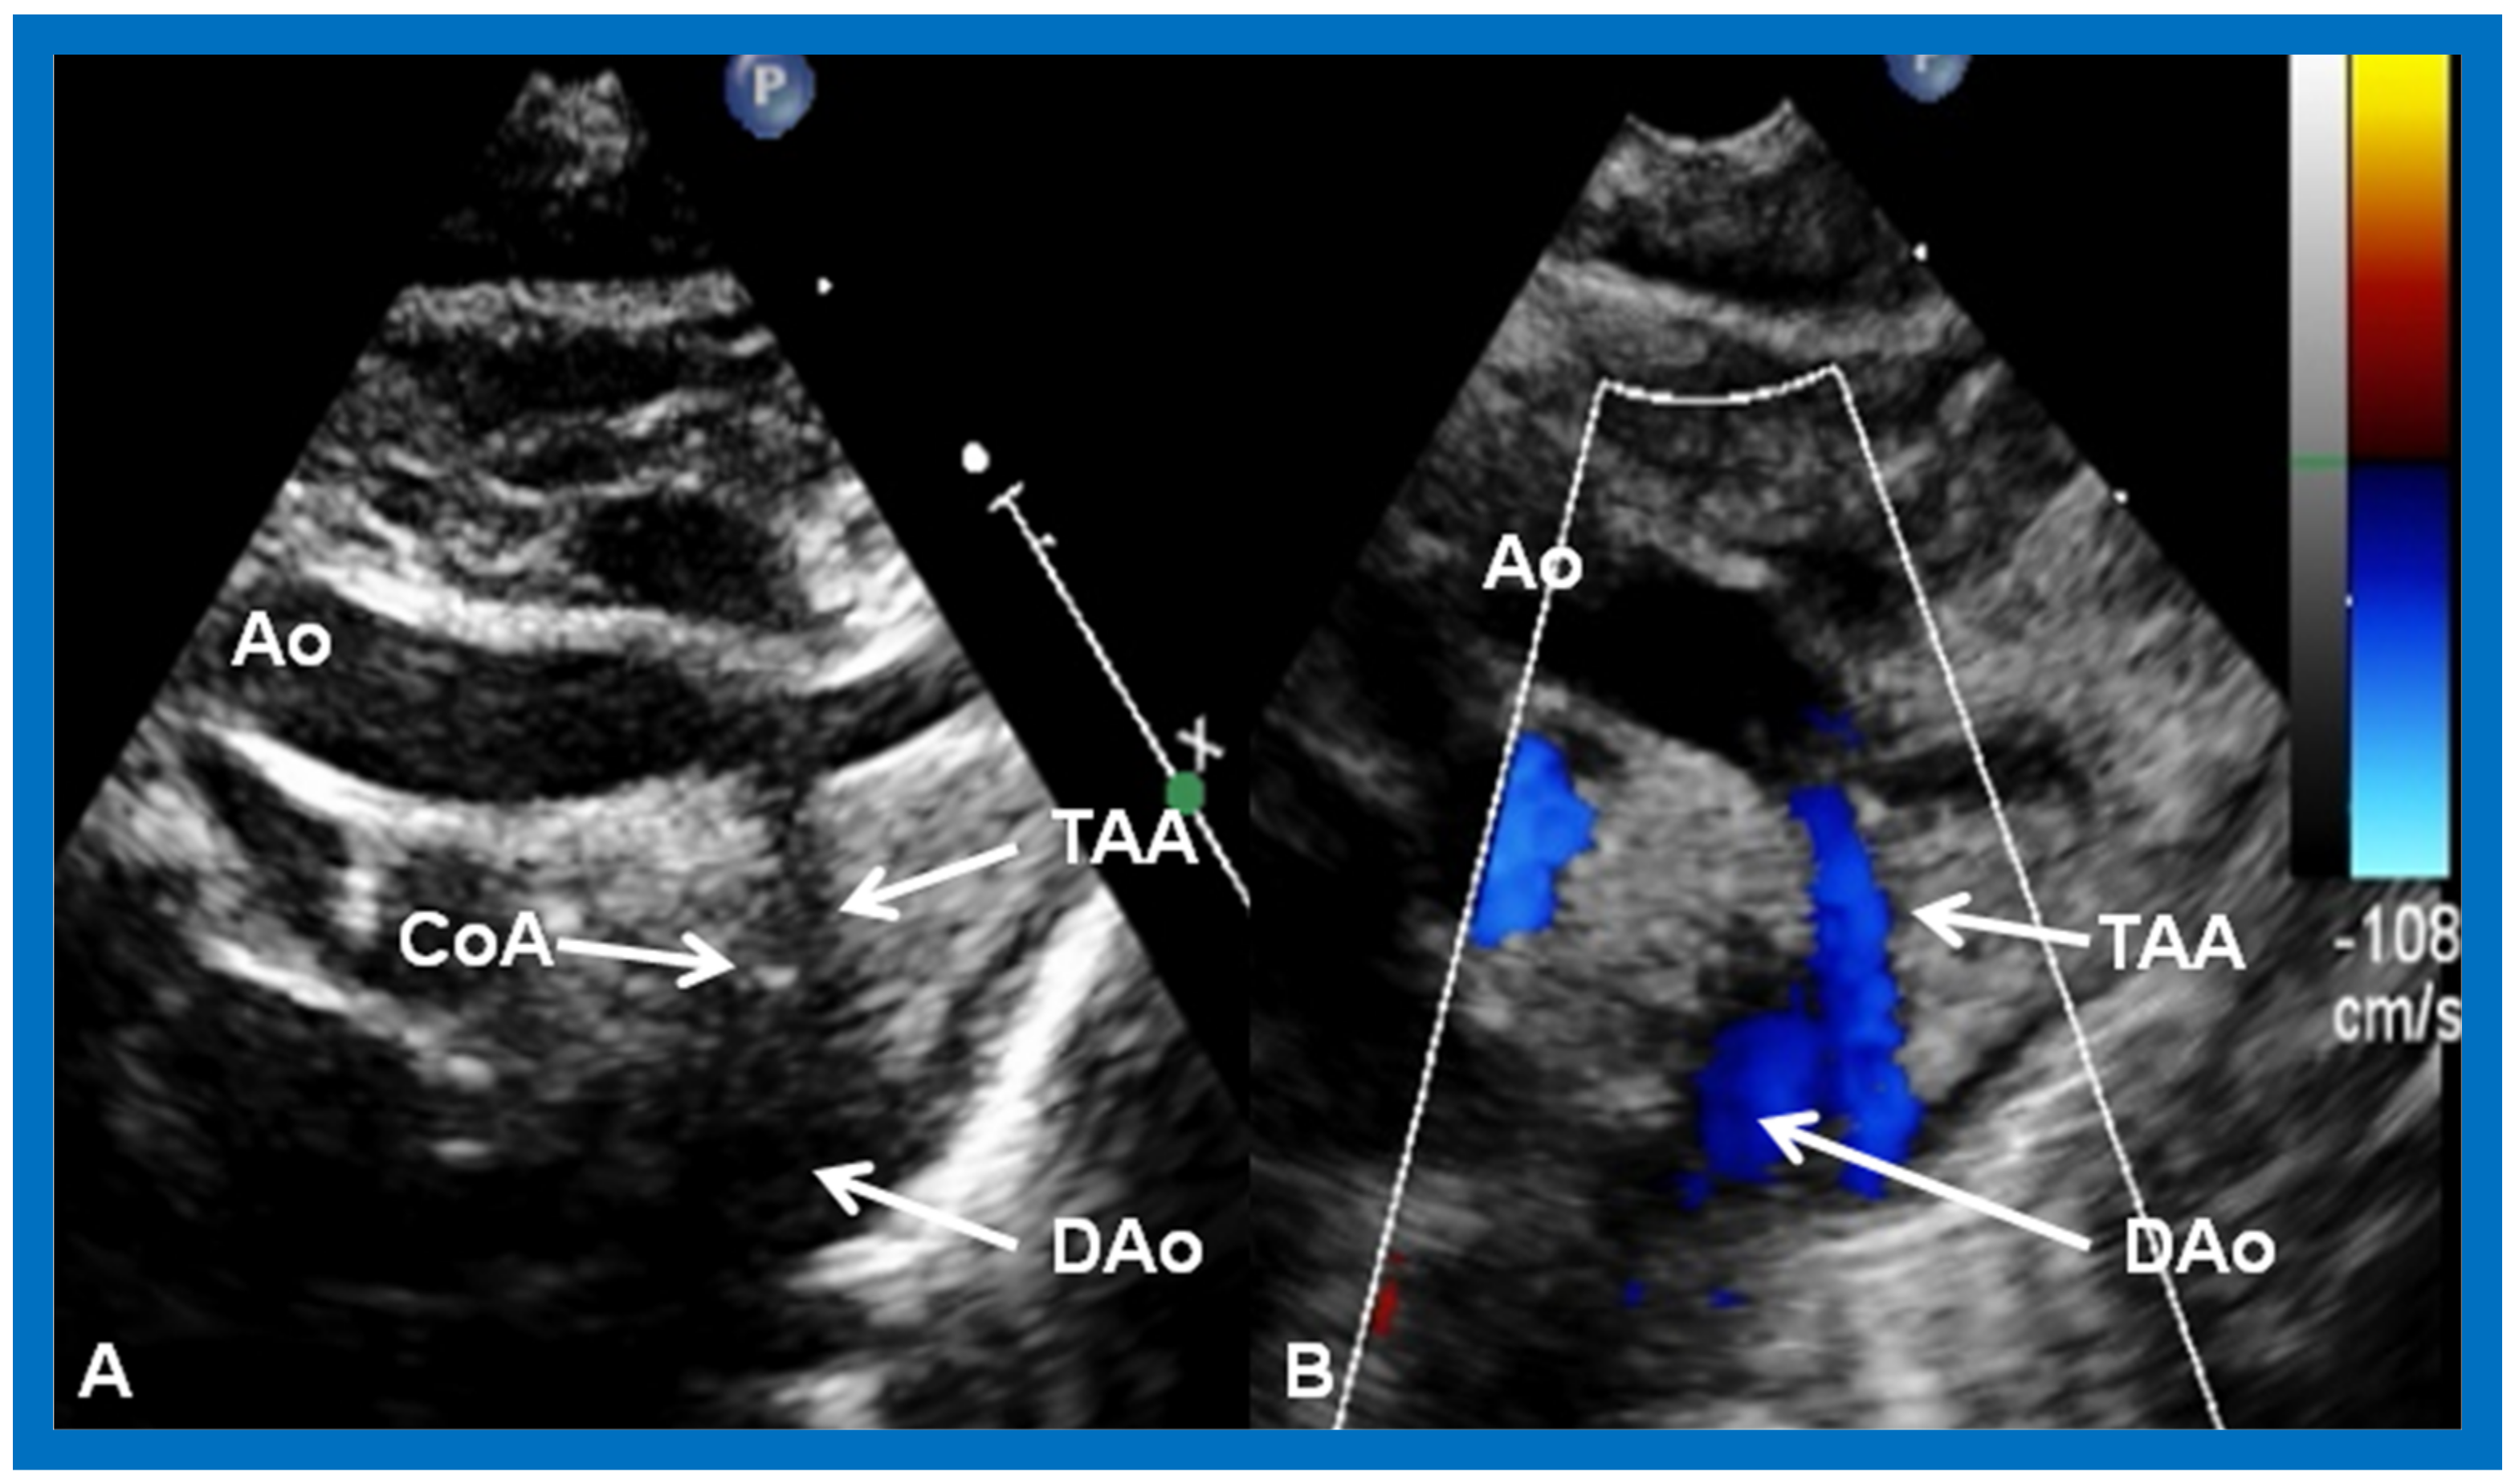

10.1.6. Aortic Arch Obstruction

Aortic Coarctation